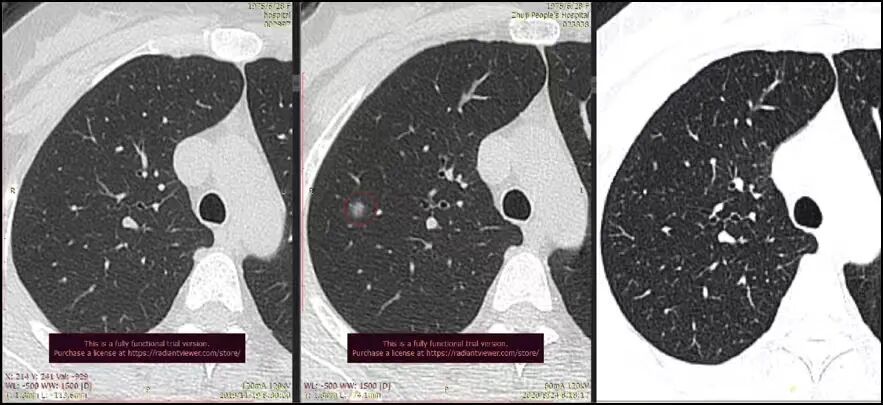

根据结节的密度不同,肺结节常被分为:

(1)实性结节:均匀高密度,明显实性成分。

(2)纯磨玻璃结节:半透明密度状,像磨砂玻璃,可以看见其中的血管、支气管等结构。

(3)混合性结节:实性与磨玻璃性质的成分共存。

一般而言,混合性结节的风险相较另外两种更高。